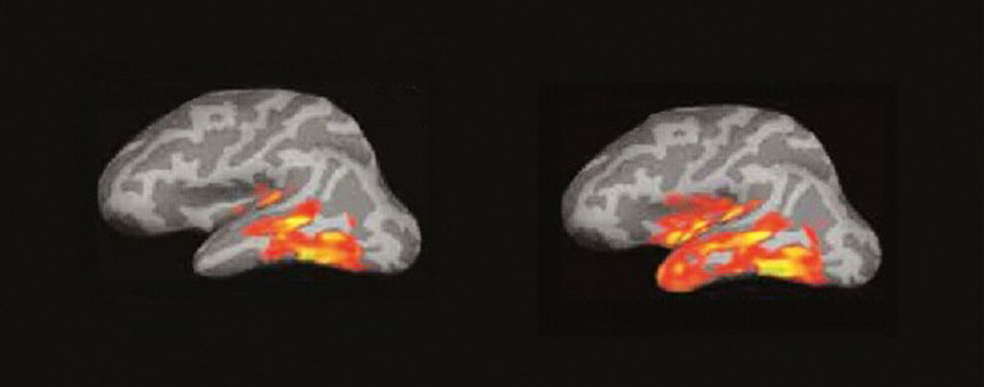

La imagen por resonancia magnética del cerebro de alguien que lee muestra algo parecido a un incendio forestal en un día de viento. Las pavesas vuelan y prenden nuevos conatos en diferentes zonas…

Entre 100 y 170 milisegundos. (A la izquierda) 1. Cuando leemos, cada palabra que ve nuestra retina produce un eco en la corteza cerebral. La primera señal eléctrica se aprecia en el polo occipital. (A la derecha) 2. La actividad se extiende a la región temporal izquierda, donde está el buzón del lenguaje, que aísla la forma visual de la palabra y la reconoce.